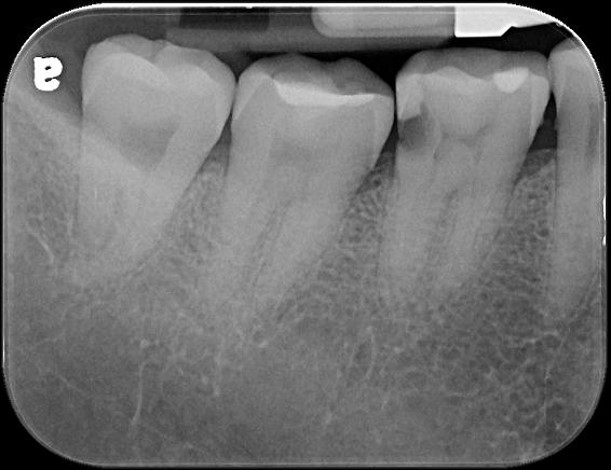

治療前,右下第一大臼齒冷熱敏感

治療前,蛀牙已侵犯至牙髓